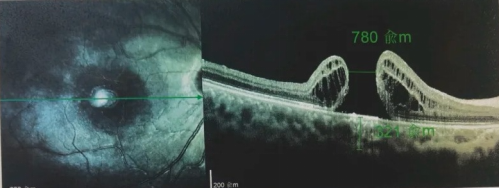

由于自身患有頸椎病,每次術(shù)后長(zhǎng)期的趴睡都讓他痛苦不堪。為了尋求更好的治療,吳爺爺來(lái)到廈門(mén)大學(xué)附屬?gòu)B門(mén)眼科中心,找到了眼外傷及眼底病2科的李海波博士后。此時(shí),吳爺爺右眼的黃斑裂孔已經(jīng)持續(xù)擴(kuò)大到780μm,演變?yōu)殡y治性的大裂孔。

最讓吳爺爺難以置信的是:術(shù)后只需保持平躺24小時(shí)!第二天復(fù)查時(shí),眼底鏡及OCT檢查清晰顯示——那個(gè)折磨了他大半年的大裂孔,竟然閉合了!且吳爺爺?shù)挠已垡暳τ辛嗣黠@的改善,術(shù)后3天已經(jīng)可以看到 0.15。

黃斑裂孔